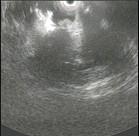

问题 患者,男性50岁,近2个月来出现中上腹隐痛,餐后更甚,伴早饱、厌食,乏力,无发热、黄疸,体重减轻了5Kg,大便隐血阳性,胃镜检查如图,则该患者最可能的诊断是 ( )

选项 A、胃癌 B、食管癌 C、消化性溃疡 D、胃溃疡出血 E、慢性胃炎

答案 A